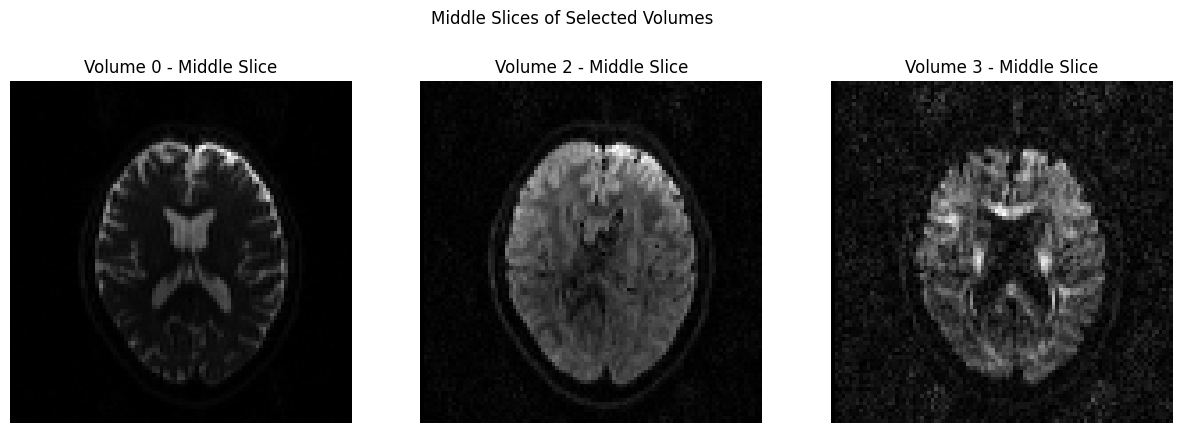

Visualization#

In order to view the image, we will use a couple of different packages, and you can determine which one you prefer. The first one we will use it matplotlib, which was loaded earlier in this notebook. In the code below, we will temporarily convert the data to NIFTI format and plot 3 volumes with Matplotlib.

volume_indices = [0, 2, 3]

slice_index = data.shape[2] // 2 # Choose the middle slice for visualization

fig, axes = plt.subplots(1, 3, figsize=(15, 5))

for i, vol_idx in enumerate(volume_indices):

# Extract the middle slice from the selected volume and rotate it 90°

rotated_slice = np.rot90(data[:, :, slice_index, vol_idx])

axes[i].imshow(rotated_slice, cmap="gray")

axes[i].set_title(f"Volume {vol_idx} - Middle Slice")

axes[i].axis("off")

plt.suptitle("Middle Slices of Selected Volumes")

plt.show()